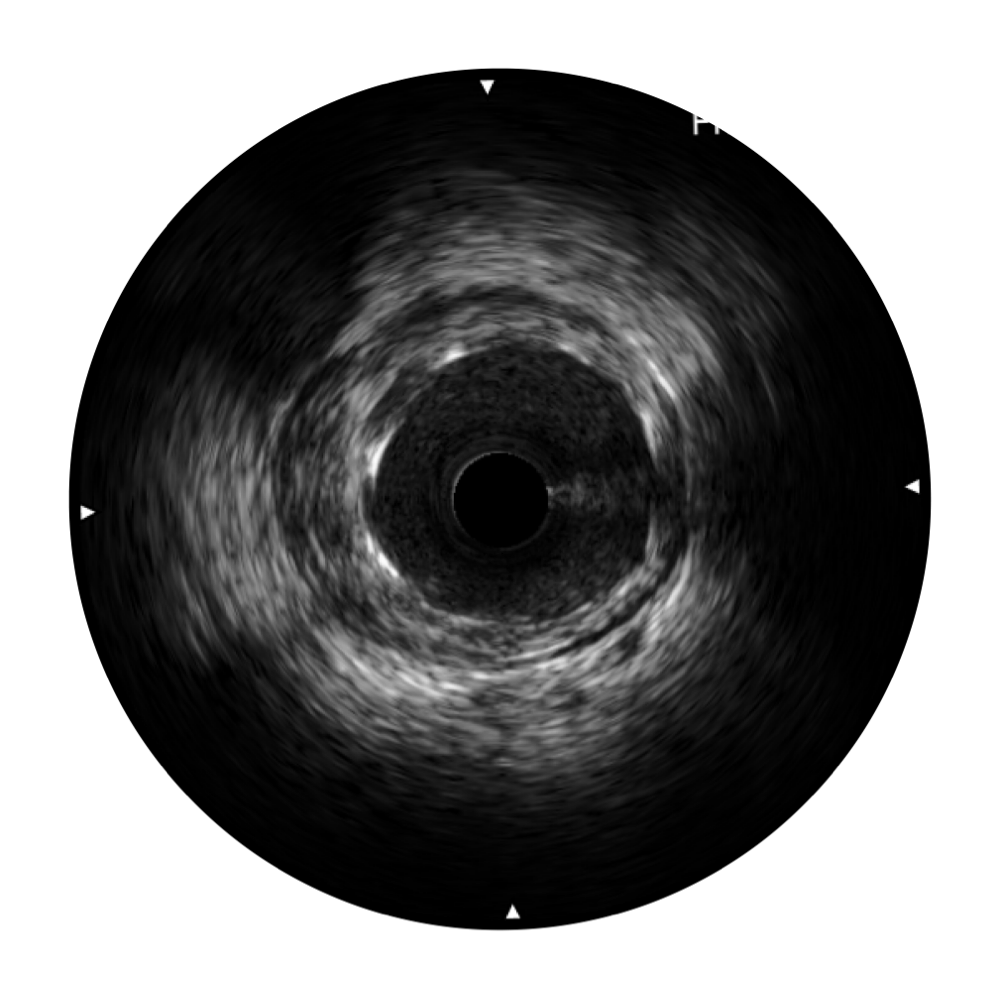

狗万官方网站宽频IVUS图像

对比传统IVUS导管成像,狗万官方网站宽频IVUS图像的近场支架梁显影更细腻,远场中膜外血管仍清晰可辨,兼顾远中近,兼顾分辨力与穿透深度